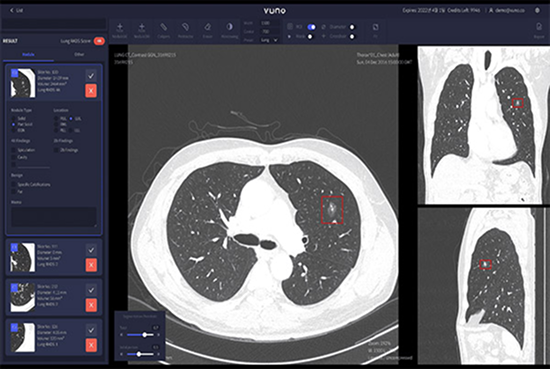

VUNO Med-LungCT’s competitive edge is about its performance. An AI-based product that assists lung diseases diagnosis, it also provides data on nodules’ size, volume, and location.

• High Sensitivity, 93% Sensitivity per 1 FP, based on performance validation with open dataset LUNA16

• Optimized nodule detection performance through super-resolution algorithm

• Detects nodules between 4mm — 30mm

• Provides volumetric data of nodules

• Provides a mask feature to detect part-solid nodules (Overall, Ground-glass, Solid Part)